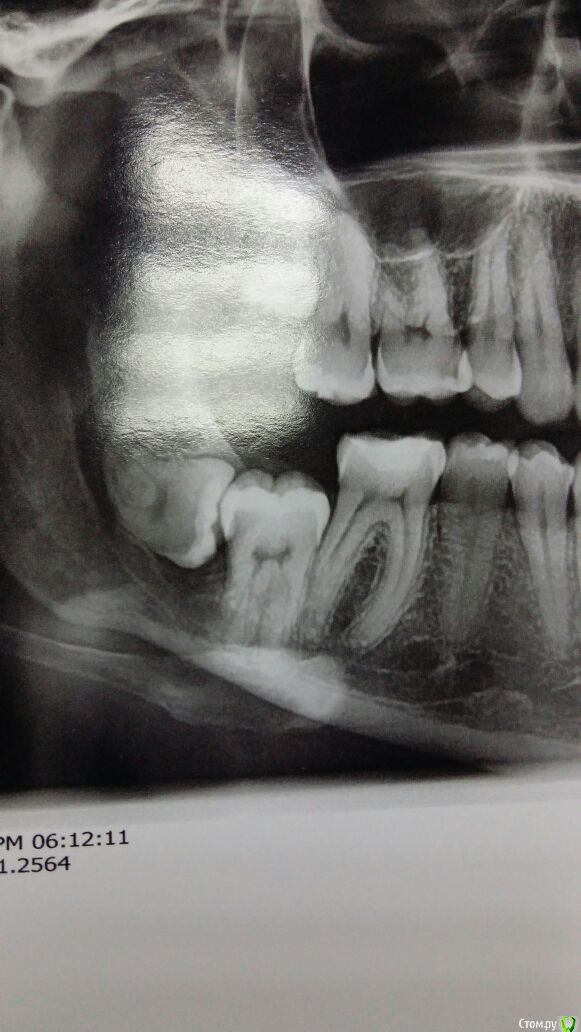

колесников Опубликовано 2 апреля, 2017 Автор Поделиться Опубликовано 2 апреля, 2017 Тройной лоскут , вид через 5 -7дней. Снимок "до". И благодарность за скорое заживление 6 Ссылка на комментарий

kriokov Опубликовано 4 апреля, 2017 Поделиться Опубликовано 4 апреля, 2017 (изменено) здесь после удаления ретенированного 48 , более менее зажило. Без изысков, доступ сулькулярно, и далее по ретромолярному. Инструмент- тот , что на столе. Шовник - ультрасорб 4\0, моно, но резорбируемый. Поэтому один из матрацных снимать не стал, концы коротко срезал и все. Видно, что где матрацный- сохраняется оверверт тканей. Клиника обычная - болело сутки, глотать больно сутки, ну и рот не очень открывался. 99% ретенированных примерно так и убираю. За качество фоток крайние извинения. столдо экзекуции , все шикарно, доступ - аэродром сразу после- ой , ой, ой , как хорошо точетверо суток-- чего то мне рана не очень, ну не очень как тоВосемь суток , это до снятия швов- ну вроде терпимовосемь суток, это уже свершилось, сняли швы. (один матрасный не снял, рассосется может быть) Изменено 4 апреля, 2017 пользователем kriokov 5 Ссылка на комментарий

колесников Опубликовано 4 апреля, 2017 Автор Поделиться Опубликовано 4 апреля, 2017 Очень даже! Коронка 8го видимо имела язычное положение? Что в лунке? Обычно проходитесь внутрибороздковым разрезом до 6го? Ссылка на комментарий

kriokov Опубликовано 5 апреля, 2017 Поделиться Опубликовано 5 апреля, 2017 8го видимо имела язычное положение? Что в лунке? Обычно проходитесь внутрибороздковым разрезом до 6го? в лунке видимо пусто, или где нибудь на дне сгусток,да , до середины коронки 6-го, примернотам просто глубоко 8-ой, но ортодонты просили убрать Ссылка на комментарий